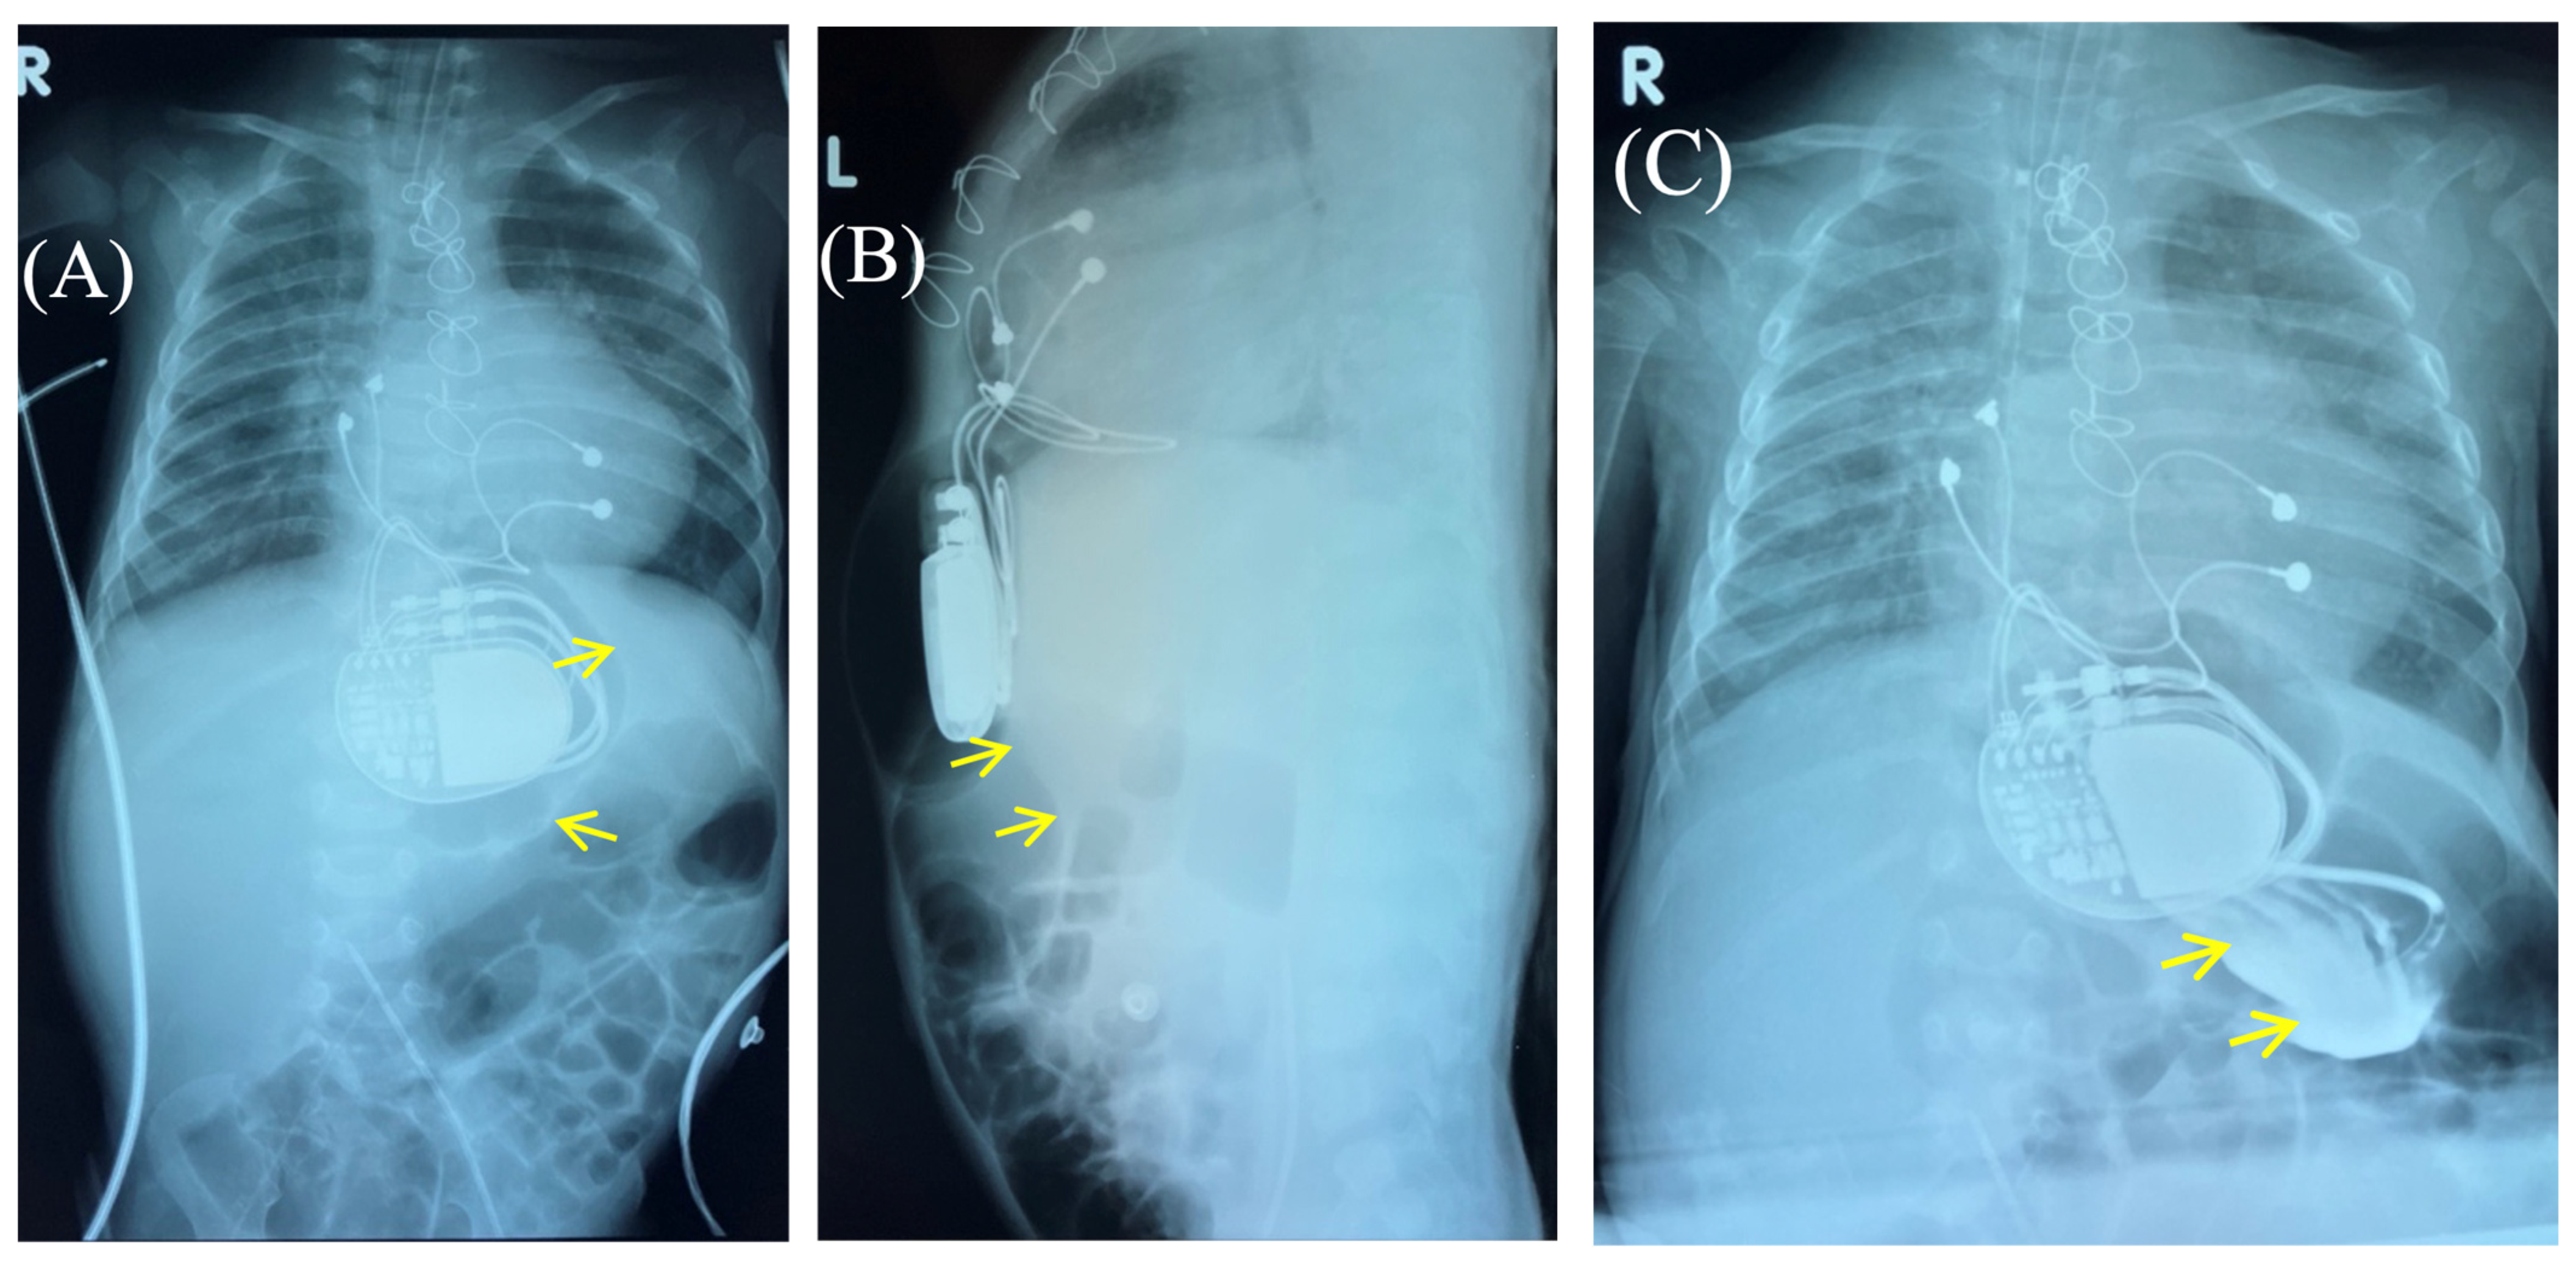

Based on the results of three wound cultures, no pathogenic flora were detected. On the seventh day, the wound was sutured, and healing proceeded without complications. The wound healed seven days after suture closure. A follow-up chest and abdominal X-ray revealed no signs of pneumothorax, pneumomediastinum, or free air in the upper anterior abdominal wall along the midline in the projection of the pacemaker pocket (Figure 6).

Figure 3. Control of the passage of radiocontrast agent (yellow arrow) through the gastrointestinal tract to exclude perforation of a hollow organ of the abdominal cavity. Frontal (A,C) and lateral (B) view of the chest X-ray 1 h (A,B) and 2.5 h (C) after radiocontrast agent administration. R: right side; L: left side.

Figure 6. Chest X-ray after surgery debridement and closure of the wound. Chest X-ray (frontal (A) and lateral (B) view) shows no signs of pneumothorax, pneumopericardium, pneumomediastinum with minimal air at the pacemaker pocket site. (C) The healed sternotomy and the projection of the pacemaker pocket 12 days after revision and sanitation.